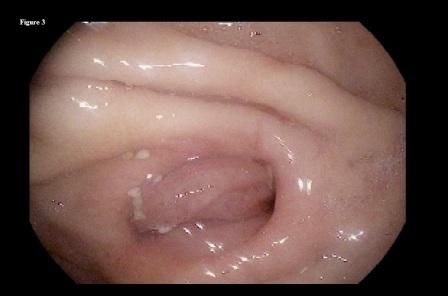

She followed this regimen for the following 3 months with significant improvement in her symptoms. A repeated upper endoscopy performed at 3 months after presentation showed complete dissolution of the phytobezoar, with a clear view of the distal end of the gastric remnant (Figure 3) and the jejunal side of the anastomosis (Figure 4).